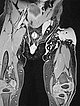

In der B-Bild-Sonographie (Bild oben) ist der Tumor relativ homogen, echoarm und klar solide, nicht komprimierbar. Die farbkodierte Duplexsonographie (Bild unten) zeigt eine starke Perfusion durch multiple arterielle Gefäße. Dies spricht für einen angeborenen vaskulären Tumor, in diesem Fall in Kombination mit dem bläulichen Erscheinungsbild für den Sonderfall eines kongenitalen Hämangioms.

Die Kontrollsonographie (FKDS) im 4. Lebensmonat zeigt keine Veränderung der Echogenität, insbesondere keine Zeichen einer Involution. Weiterhin starke Perfusion und keine Zunahme der Echogenität, wie das bei einem rasch involutierenden kongenitalen Hämangiom (RICH) der Fall wäre.